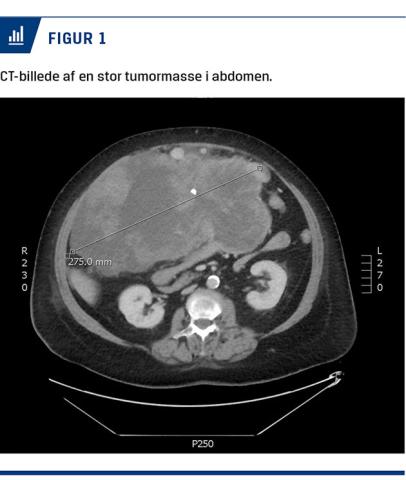

Objektivt fandt man udfyldning i abdomen, hvilket patienten var under udredning for, idet hun over fire måneder havde taget 17 kg på og havde tyngdefornemmelse. En CT havde vist en tumor, der udgik fra ventriklen og målte 30 × 17 × 25 cm (Figur 1), det drejede sig formentlig om en gastrointestinal stromatumor, men der var endnu ikke svar på en biopsi.